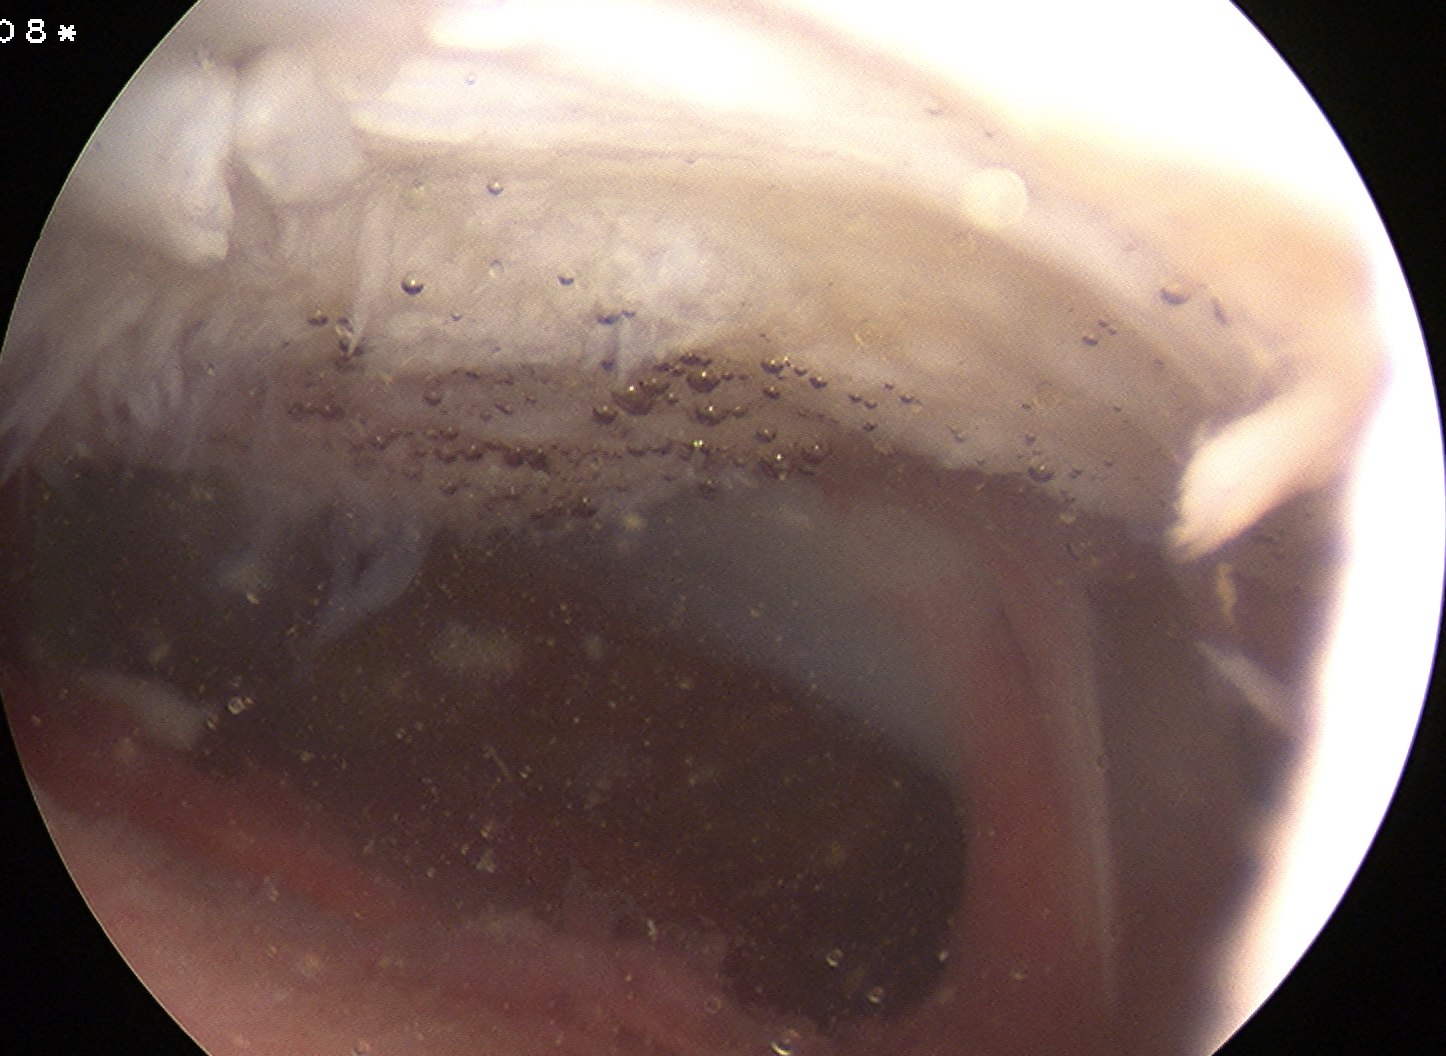

Arthroscopy

Synovial proliferation

- localised or generalised

- can see cartilage growing from synovium

Multiple loose bodies +++